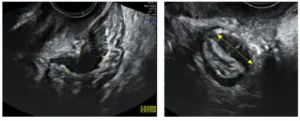

- La ecografía ginecológica realizada por manos expertas, que hoy en día se considera una técnica adecuada, precisa y suficiente para el diagnóstico en la mayoría de los casos, sin necesidad de recurrir a cirugía.